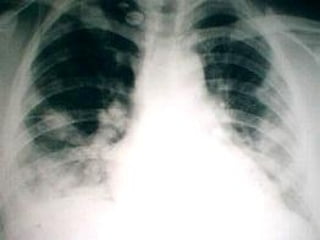

Infiltrado intersticial retículo nodular bilateral de predominio perihiliar y basal